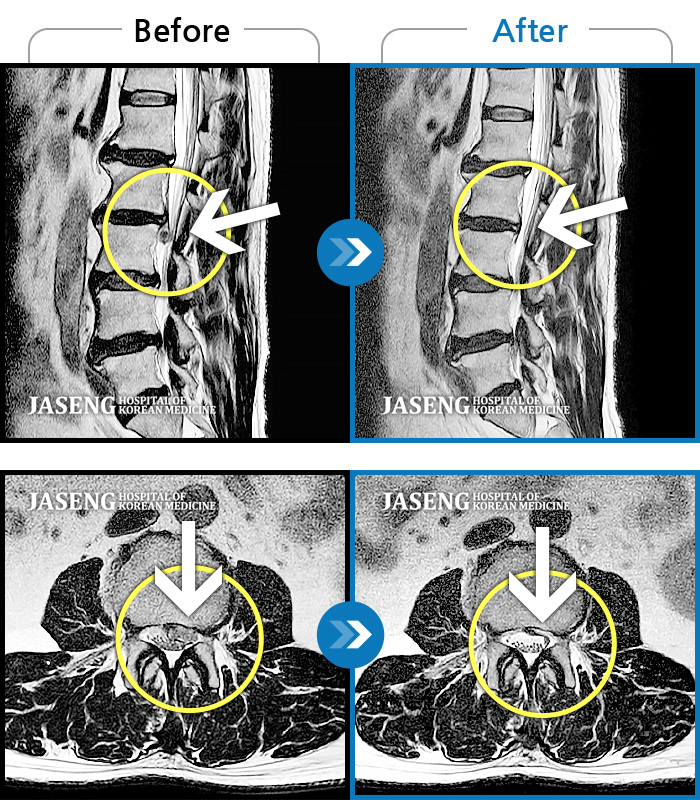

허리디스크

천안 · 윤영웅 원장

허리와 좌측 다리 통증저림이 심하고 발목 힘이 빠져요.

촬영시기

2021.09.17 ~ 2022.04.30

2022.05.02